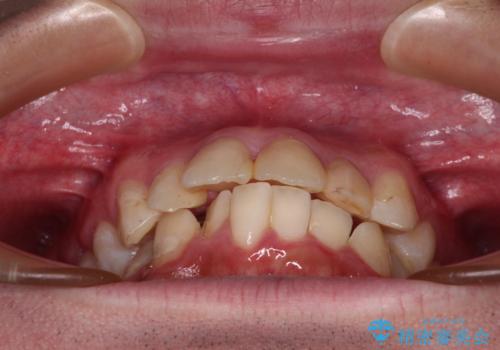

- 口元の突出感と奥歯の咬み合わせの悪さを気にして来院された患者様です。

口元はやや突出感があったため、上下左右の第一小臼歯4本を抜歯してワイヤー矯正にて抜歯矯正を行うこととしました。

また、左右ともに最後臼歯が交叉咬合になっており、外側に飛び出している上顎の最後臼歯を補助装置を利用して、積極的に内側に引き込むようにしました。